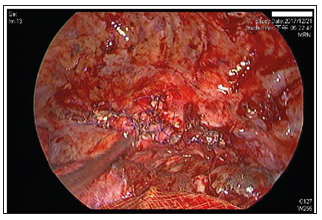

The patient reported no other significant chronic medical history, such as diabetes mellitus, any type of heart disease, disturbed microcirculation, peripheral neuropathy, immunocompromise, malignancies, leukaemia, long-term use of corticosteroids, liver cirrhosis, renal failure, urinary tract infection, or haemodialysis (Figure 4). He also reported no history of infection, such as tuberculosis, any type of hepatitis, or acquired immunodeficiency syndrome (AIDS). He had undergone TEVAR and several blood transfusions as previously mentioned, and he had no prior history of traumas or other serious events in his medical history. He did not live in an epidemic area and had no history of toxin or radiation exposure. He was previously a businessman and had been retired for 8 years. Physical examination (PE) revealed an elderly male who was conscious, awake and alert but in moderately painful distress with apparent generalized anxiety despite previous treatment with intravenous morphine (10mgq4hprn) and risperidone (1mghs). He was intubated with a fraction of inspiration O2 (FiO2) of 50% and a positive end-expiratory pressure (PEEP) of 7cmH2O under synchronized intermittent mandatory ventilation (SIMV) mode control.

Figure 4: Interoperative image of the third surgery. Primary closure of oesophageal defect was performed with 4-0 Prolene in an interrupted suture pattern witSh a residual aortic granulation tissue buttress.